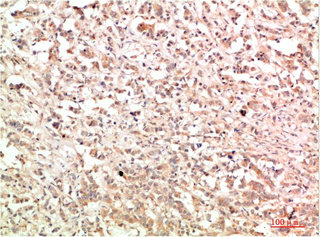

• Immunohistochemical analysis of paraffin-embedded Human Breast Carcinoma Tissue using c-Abl Rabbit pAb diluted at 1:200